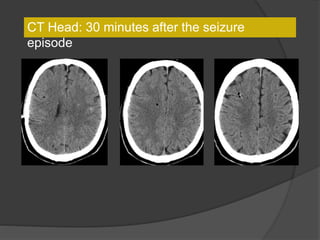

CT Head: 30 minutes after the seizure

episode

24 hrs laterLeft hemiparesis resolved

Partial resolution of air foci and appearance of hemorrhagic infarcts, also had

metastases in the brain explaining other hemorrhages

Dx: Cerebral air embolism and small

hemorrhagic infarcts

 Can occur during bronchoscopy when a

patient exhales or coughs against a

wedged bronchoscope with local

pressure increase and disruption of local

capillary network. Treat with hyperbaric

oxygen.

 Other causes include GI endoscopy,

barotrauma, central venous catheters,

CV surgery